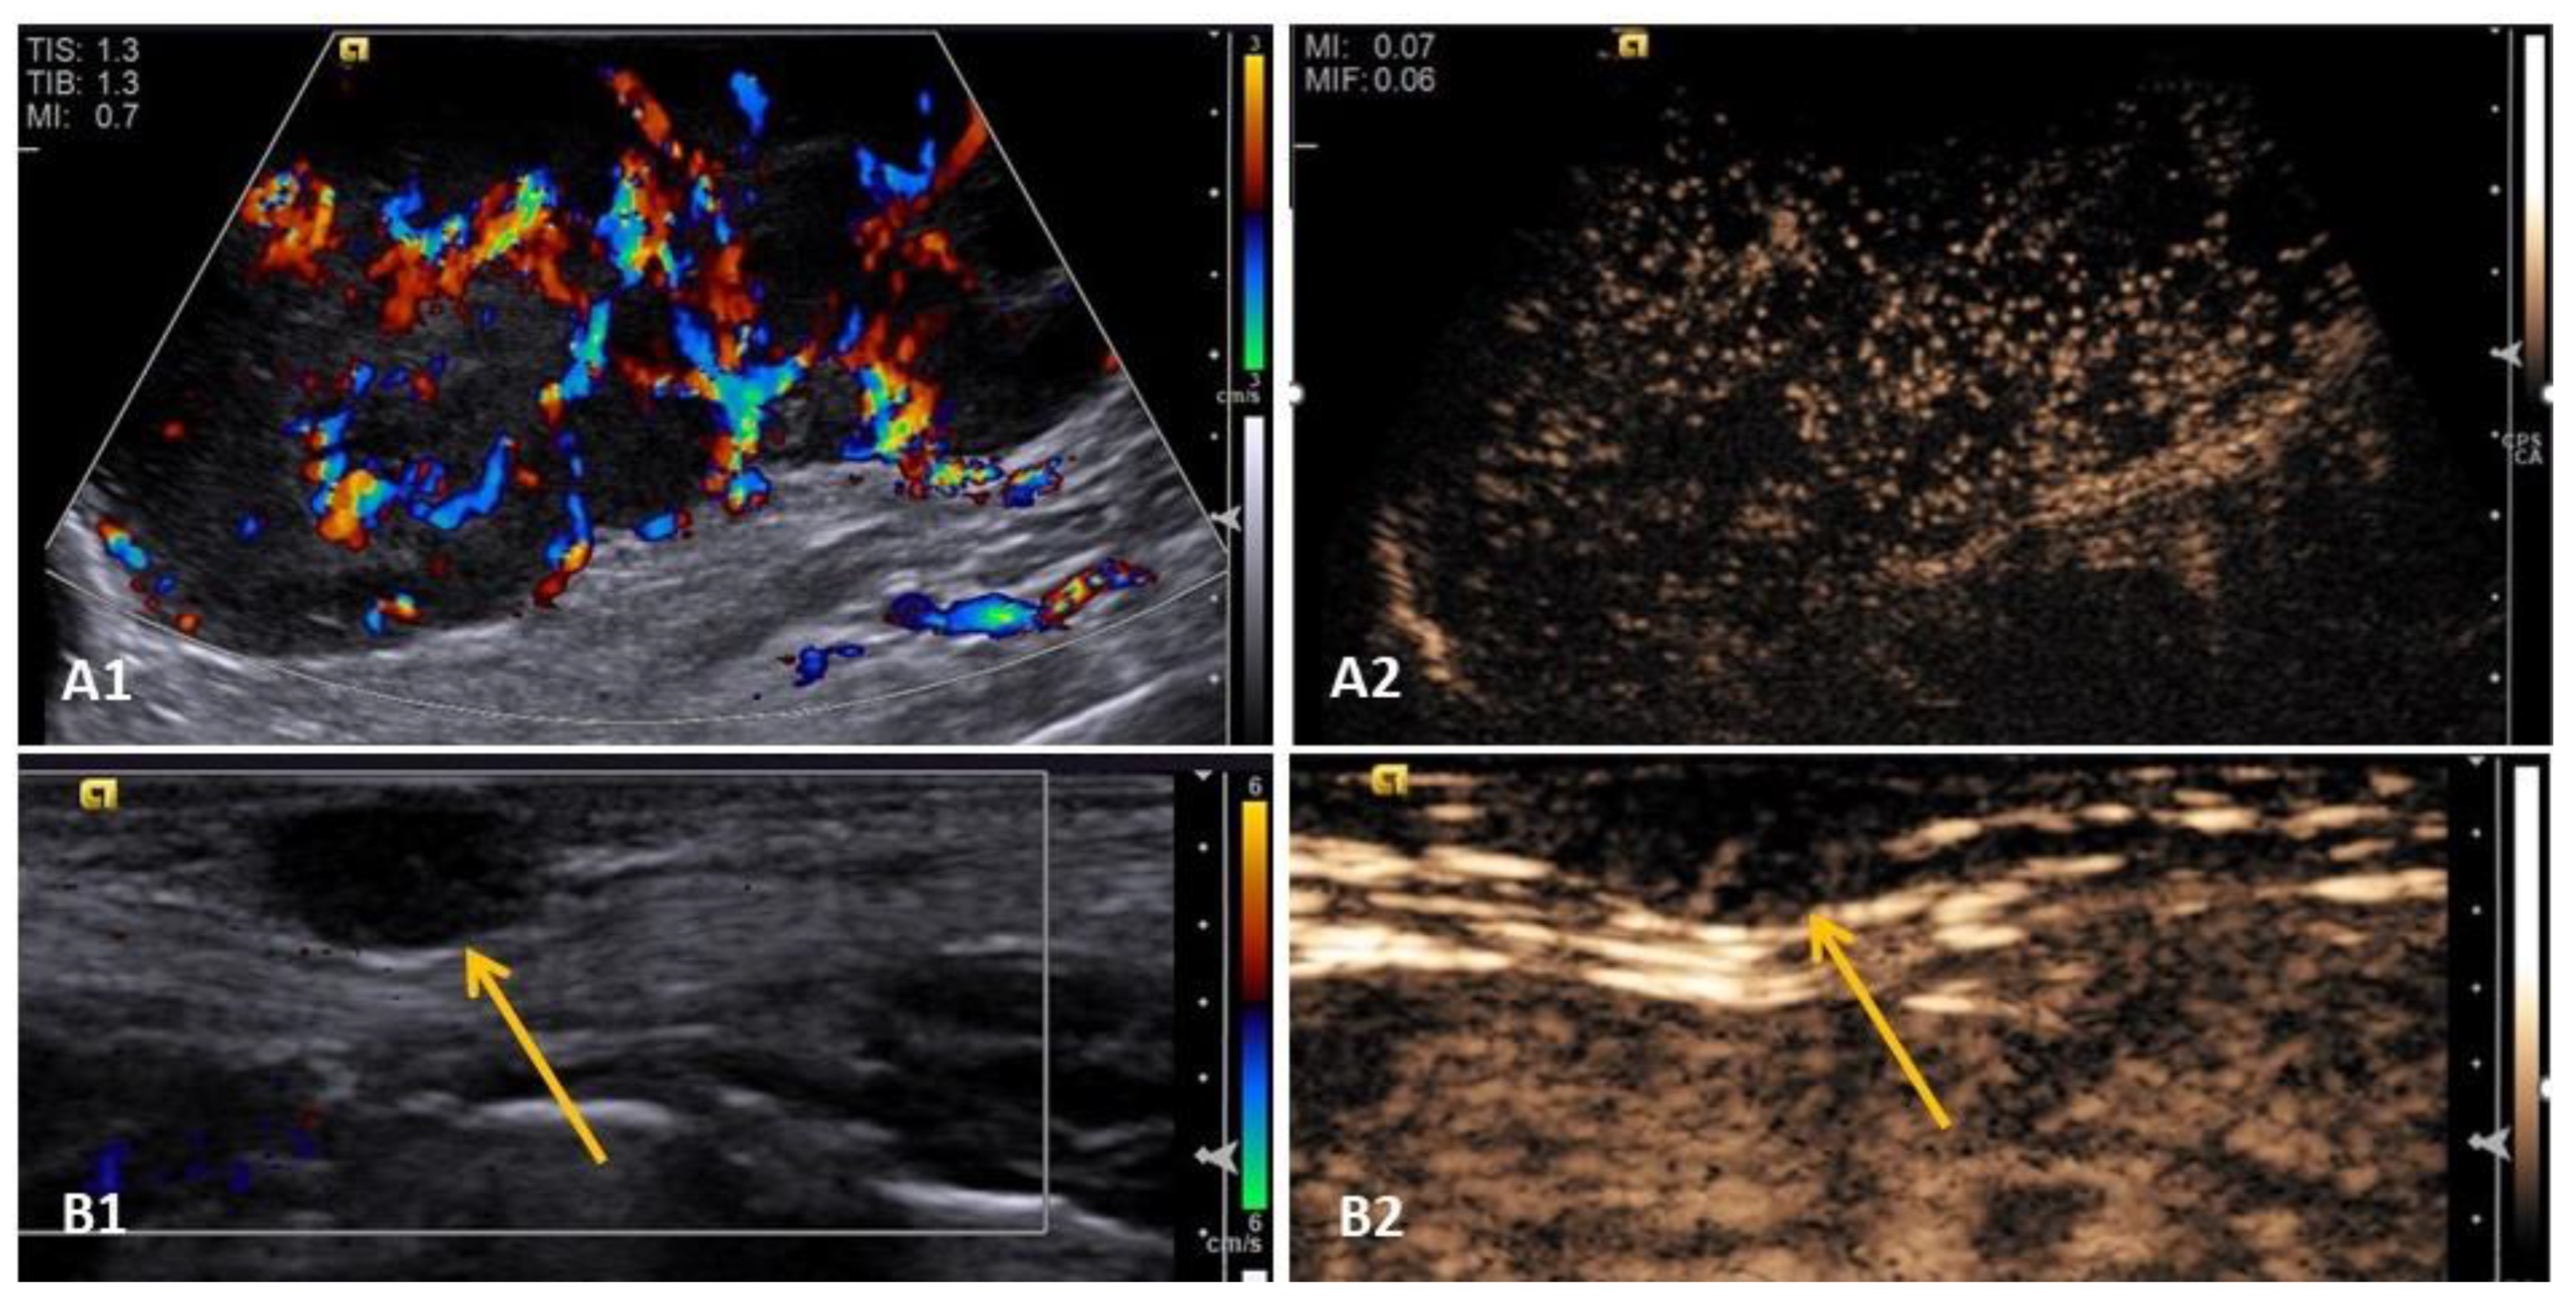

3.4. Contrast-Enhanced Ultrasound (CEUS)

- Hillaert, A.; Stock, E.; Duchateau, L.; De Rooster, H.; Devriendt, N.; Vanderperren, K. B-Mode and Contrast-Enhanced Ultrasonography Aspects of Benign and Malignant Superficial Neoplasms in Dogs: A Preliminary Study. Animals 2022, 12, 2765. [Google Scholar] [CrossRef]

- Abma, E.; Stock, E.; De Spiegelaere, W.; Van Brantegem, L.; Vanderperren, K.; Ni, Y.; Vynck, M.; Daminet, S.; De Clercq, K. Power Doppler ultrasound and contrast-enhanced ultrasound demonstrate non-invasive tumour vascular response to anti-vascular therapy in canine cancer patients. Sci. Rep. 2019, 9, 9262. [Google Scholar] [CrossRef] [PubMed]